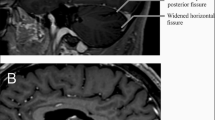

Therefore, in cases of late-onset ataxia, especially when coinciding with sensory neuropathy, it is advisable to conduct screening for biallelic RFC1 expansions [14]. Cerebellar atrophy, which is defined clearly as a diminution of vermian Purkinje cells, is the most prevalent MRI result; however, there may be other, less frequent, related abnormalities as well [17, 31, 32]. In addition to the cerebellum and its connections, the basal ganglia dopaminergic circuitry is also affected by neurodegeneration in RFC1/CANVAS. It is recently discovered that RFC1/CANVAS frequently exhibits nigrostriatal dysfunction [33, 34]. Subsequent symptoms may also include the development of orthostatic hypotension, neuropathic pain, dysphasia, dysarthria, challenges with urinary erectile, retention functions and dryness in eyes and mouth [22, 32, 35]. A recent study by El Houjeiry et al. described the first case of CANVAS syndrome which was initially presented with isolated spinal cord lesion which mimicked dysimmune myelitis [36]. Very recently, another study reported two cases of RFC1-associated CANVAS with the brain MRI illustrating the (pseudo-)eye-of-the-tiger sign [31]. In fact, this study highlights that RFC1-associated CANVAS should be considered as an alternative imaging diagnosis in cases exhibiting the (pseudo-) eye-of-the-tiger sign. This finding expands our understanding of potential differential diagnoses in imaging studies. Thus, the prevailing features now indulge more than just the classical triad of symptoms; they also encompass an enduring chronic cough, along with discernible signs of dysautonomia and neurogenic pain. These revelations contribute to a more profound comprehension of this condition and its diverse expressions, offering a path towards more focused and efficacious medical interventions.

From a neuroscientific perspective, CANVAS can be characterized as a neuronopathy implicating the dorsal root ganglia, multiple cranial nerve pathways and concomitant cerebellar atrophy. Figure 3 clearly defines the three primarily associated clinical features along with their distinct characteristics. Dorsal root ganglionopathy is now considered to be responsible for sensory impairment in CANVAS, which leads to degeneration of neuron cell bodies [32, 37]. The sensory dysfunction in CANVAS does not adhere to the typical length-dependent paradigm often seen in neuropathies. Distinctively, CANVAS demonstrates a non-length-dependent sensory deficit, clinically described as sensory ganglionopathy or neuronopathy, marking its unique pathophysiological profile [38]. In a study conducted by Szmulewicz et al., which explored the neuropathology of the brain and spinal cord in two individuals diagnosed with CANVAS, it was observed that the sensory deficit results from dorsal root ganglionopathy accompanied by secondary tract degeneration [17]. Scarpa ganglion cells also exhibited reduction [39]. The sensory deficit’s pathology stems from the neuronal loss in cranial nerve V, VII and VIII ganglia, as well as the dorsal root ganglion in the spinal cord. Neuronal loss in the dorsal root ganglion leads to axonal degeneration, subsequent removal of the myelin sheath, and T2 hyperintensity in the posterior columns of the spinal cord [17]. Post-mortem temporal bone histology revealed ganglionopathy in facial, vestibular and trigeminal nerves [37]. In the investigative examination of cerebellar sections, a notable reduction of Purkinje cells and vermal atrophy was observed, associated with the formation of torpedo bodies. Additionally, gliosis of the Bergmann layer was discerned [37]. The research team identified neuronal loss in the inferior olivary nuclei of the cerebellum, which correlates with the sensory deficits. The axonal degeneration coexisted with nerve thinning [40]. Consequently, the cross-sectional area of peripheral nerves in these subjects was significantly reduced in comparison to healthy controls. Further, degenerative changes within the nuclei of the pons and evident neuronal loss characterized the CANVAS patients [41]. The potential degeneration of the mesencephalic nucleus has also been accounted for by the observed masseter areflexia. Vermal involvement pattern causes Crus 1 to act functionally analogous to the oculomotor region of the cerebellum [42]. Vestibular system pathology is linked to the loss of vestibular ganglion, termed vestibular neuronopathy, observed in all five temporal bones, along with atrophy of vestibular nerves in axons and dendrites [39]. Notably, the vestibular nuclei and receptor cells remain unaffected, and there is no evidence of trans-synaptic degeneration [42]. The maintenance of the vestibular nuclei, despite the degeneration of axons, is due to the varied afferent nerve inputs they receive, including those from the visual system and the midbrain [39]. Additionally, sensory nerve damage in the geniculate and trigeminal ganglia, as observed in two temporal bones, contributes to the profound vestibular impairment in CANVAS patients, attributing it to vestibular ganglionopathy [39]. Auditory functions remain intact, given that neither degeneration nor neuronal loss is observed in the cochlear ganglia and auditory nerves. The front and side sections of the spinal cord, along with the thoracic columns, have known to stay intact or unaffected. Additionally, fossa decompression emerges as a potential complication associated with bilateral vestibulopathy [22].